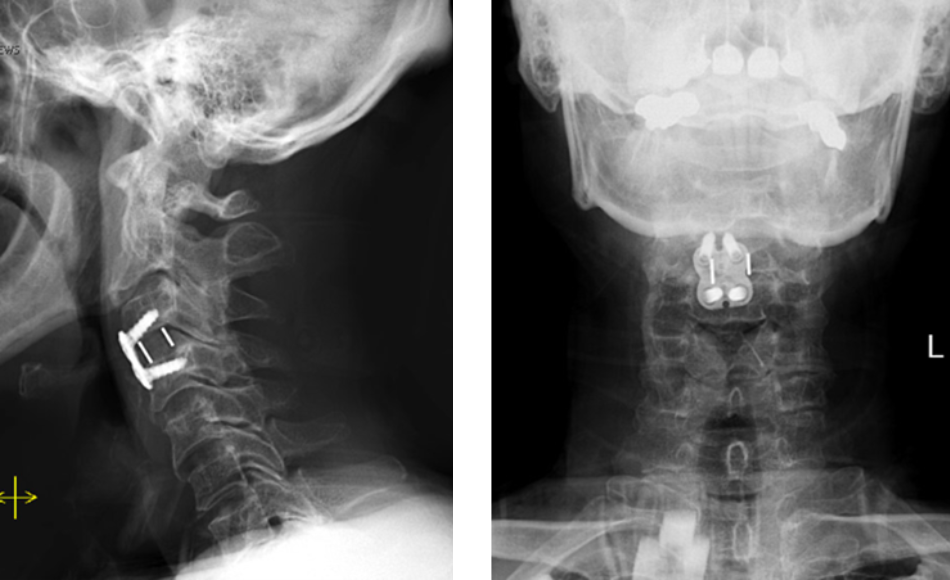

Back:

Revision Surgery Treats Intractable Neck Pain & Cervical Deformity

Author: Benjamin R. Cohen M.D., F.A.A.N.S., F.A.C.S., Read More!